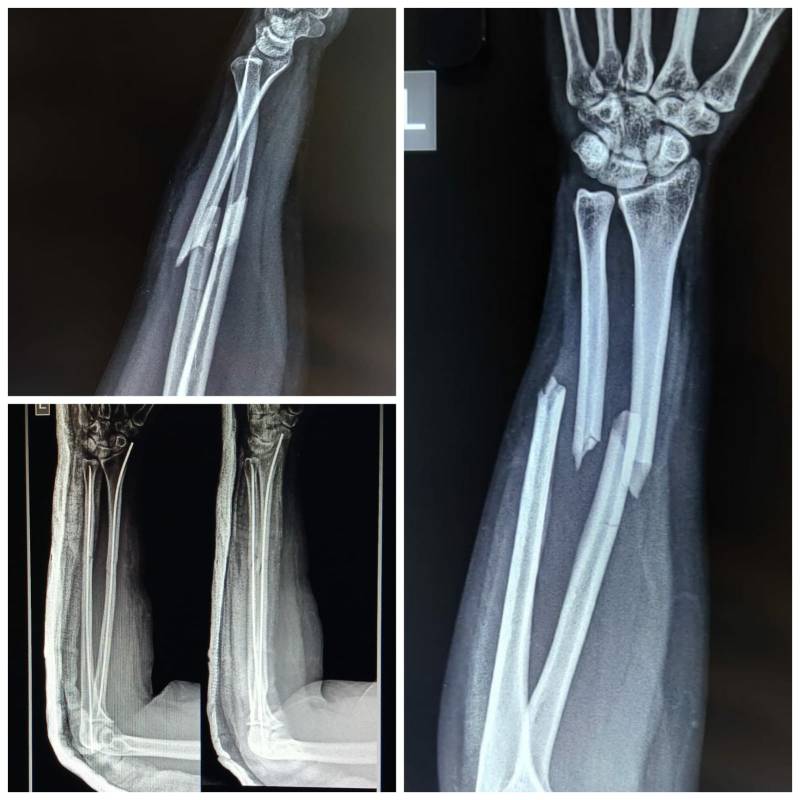

#Fractured both forearm bones. Radius and ulna are both bones in forearm. They can be fractured in case of fall/accident. In adults such fractures require plate fixation of nail fixation. This case has nail fixation advantage being it's done in just single stitch . No additional muscle dissection leads to faster recovery!! After all as patients and doctors that is all we want!!